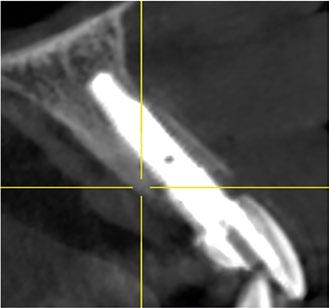

Su solicitud inicial es volver a blanquear el 21, que había sido previamente endodonciado y había recibido sucesivos tratamientos blanqueadores que habían recidivado. Refiere ligera molestia en la papila interincisiva. En la exploración radiográfica intraoral 1 2

se aprecia una extensa reabsorción radicular interna, con el consiguiente defecto óseo, que se confirma con un CBCT (Fig. 3, 4, 5). Se informa a la paciente del riesgo de fractura espontanea. Esta solicita solucionar el problema antes de que avance más.

El plan de tratamiento propuesto es, previa planificación digital, la reposición postextracción del 21, relleno del gap bucal, injerto conectivo subepitelial y provisionalización inmediata. Tras 4 meses iniciar la fase de acondicionamiento final del tejido blando y a los 6 meses prótesis definitiva. Planificación digital de la posición ideal del implante y fabricación de la guía quirúrgica y corona provisional (Fig. 6 y 7).

En la exploración radiográfica en 3D (CBCT) se aprecia ausencia de cortical vestibular en 2.1 y un defecto óseo horizontal en 1.1 (Figura 3).